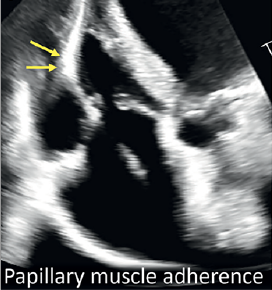

Dr. Hahn: Tricuspid valve anatomy is very complex. Only about 50% of tricuspid valves have three leaflets and the remainder can have anywhere from two to even greater than five leaflets.12 The most common non-trileaflet morphology is a four-leaflet tricuspid valve, so it is somewhat of a misnomer. In that setting, there are a lot of chordae and we believe that the greater the number of leaflets, the greater the number of papillary muscles. Therefore, the complexity of the leaflets, the complexity of the chordal apparatus, and the complexity of the subvalvular papillary muscles are all risks for the pacemaker interacting with those parts of the anatomy. The way that the electrophysiologist places the lead may have something to do with whether or not we will eventually get interaction with any of the complex tricuspid valve apparatus. In the consensus document, we show examples of pacemakers that are adherent to papillary muscle, to the chordal apparatus, as well as to the leaflets, so it is not necessarily an isolated leaflet problem. All of those interactions will affect the way that the leaflets are able to close and therefore, may cause TR. If the lead is adherent to the leaflet and the primary cause of TR, then those patients tend not to be T-TEER candidates. However, there are patients within the trials, although we haven’t evaluated this extensively, that had leads with some form of lead interaction with the tricuspid valve apparatus and they were still able to have a T-TEER device placed.

3-Dimensional transthoracic echocardiographic reconstruction of the tricuspid valve is used to determine the location of the cardiac implantable electronic device (red asterisk) to show (A) septal leaflet impingement, (B) anterior leaflet adhesion, and (C) posterior leaflet adhesion. Apical 2-dimensional imaging windows additionally may show lead adherence (yellow arrows) on the (D and E) septal leaflet (2- and 3-dimensional, respectively) and (F) papillary muscle (color Doppler with tricuspid regurgitation in G). (H) Subcostal windows may also be diagnostic of valvular or subvalvular impingement (red arrow). (I) Thrombi on leads (red circle) may result in pulmonary hypertension and tricuspid regurgitation.

A, 1⁄4 anterior leaflet; LP, 1⁄4 leadless pacemaker; P, 1⁄4 posterior leaflet; RA, 1⁄4 right atrium; RV, 1⁄4 right ventricle; S, 1⁄4 septal leaflet.

Reprinted with permission from Hahn RT et al; Heart Valve Collaboratory and Heart Rhythm Society. J Am Coll Cardiol. 2024 May 21;83(20):2002-2014.